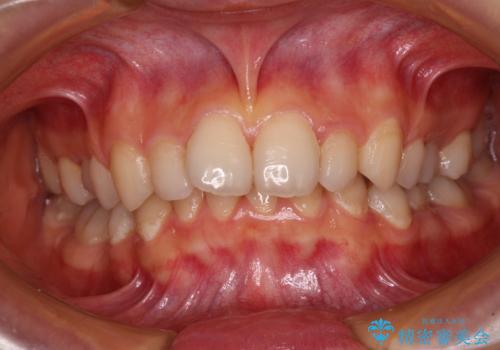

捻れて前に出ている前歯 ワイヤー装置での非抜歯矯正